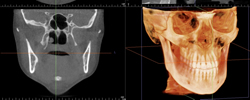

最新のレントゲン、CTを完備し、より正確で安全に治療いたします。